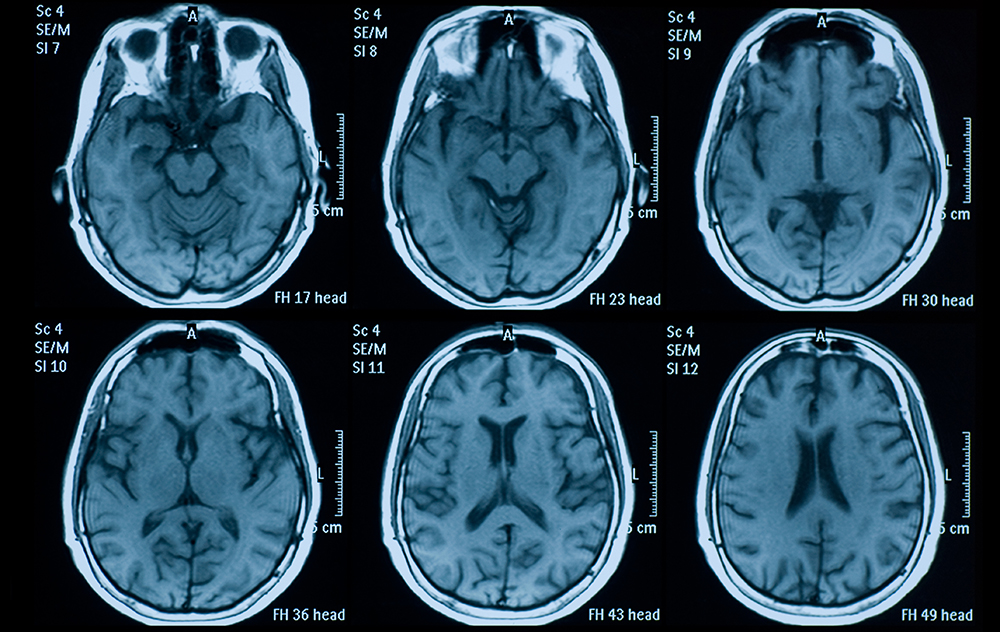

Brain MRI

If you look closely at the brain of a person suffering from Alzheimer’s or dementia, you can see the differences. Structurally, there is atrophy—shrinking in the cerebral cortex and hippocampus—and enlarged ventricles.

Doctors don’t diagnose Alzheimer’s or dementia solely through MRIs. There are tests and assessments, but the scan is a part of the puzzle that can help greatly in diagnosis and treatment.

For conditions like Autism Spectrum Disorder, however, there is no equivalent. While there are some physical differences in a brain with ASD, the exact relationship between the differences and the symptoms is unclear. As a result, the 75 million children with ASD worldwide are diagnosed solely by therapists.

That could change however. While researchers are still looking for clear structural biomarkers associated with autism, there are functional differences that can leave clues. For the past year, psychology and computer science and engineering major Nick Luckenbach ’22 has worked in Professor Lang Chen’s lab, using machine learning to analyze open-source functional MRI brain scans. By turning these scans into data, Luckenbach hopes artificial intelligence can teach us more about how brains with ASD function and, in turn, help doctors diagnose ASD earlier and potentially offer more effective treatment.

Typically, ASD is diagnosed by a therapist because it’s very behaviorally driven. The therapist goes through a list of behaviors or difficulties a patient might be exhibiting and makes a diagnosis. With neuroimaging, we’re trying to see if we can come up with a brain-based understanding of ASD in addition to the behavioral one made by the therapist. Essentially, we’re taking a thousand fMRI brain scans—which measure brain activity by detecting changes associated with blood flow—and using high-performance computing available at SCU (WAVE) to analyze the correlations of brain networks.